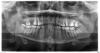

SergioS Опубликовано 14 февраля, 2013 Поделиться Опубликовано 14 февраля, 2013 Прошу помощи разобраться:Пациентка была у терапевта:30.01.- орто,44 под витапекс, временная пломба. перкуссия 44 болезненна2.02. - осмотр болит меньше.9.02 - боли усилились перкуссия 45 резко болезненна, 45 под Vitapex. Амоксиклав.12.02. - мой прием: Из анамнеза 3 дня назад перенесенная ветрянкатемпературы нет, ассиметрия лица(отек щечной области справа), гиперемии кожн покровов нет. Слизистая в области 46-43 со щечной сторны гиперемирована.отечна, флуктуации нет. 46 - подвижность 0-I степени. Перкуссия 46,45.44,43 резко болезненна. Что предпологаете? Мне еще корни 46 не нравятся(короткие они(я понимаю.что Попова-Годона). Ссылка на комментарий

SergioS Опубликовано 14 февраля, 2013 Автор Поделиться Опубликовано 14 февраля, 2013 44 причина. Чего мудрить то? насчет корней 46 ничего не понял. Чем они вам не нравятся? Откуда какой Попова-Годона?Корни 46 короче, чем 47 и 36. Зубо-альвеолярное выдвижение(попова-годона) присутствует на 46. Ссылка на комментарий

Большой Зеленый Опубликовано 14 февраля, 2013 Поделиться Опубликовано 14 февраля, 2013 Корни 46 короче, чем 47 и 36. Зубо-альвеолярное выдвижение(попова-годона) присутствует на 46.Вы путаете его с кем то?))Это бывает при отсутствии антагонистоввыглядит вот такhttp://i011.radikal.ru/1302/ab/087ff0f932d4.jpg 2 Ссылка на комментарий

johniola Опубликовано 14 февраля, 2013 Поделиться Опубликовано 14 февраля, 2013 попова -годона есть на 27 а на 46 не вижу Ссылка на комментарий

SergioS Опубликовано 14 февраля, 2013 Автор Поделиться Опубликовано 14 февраля, 2013 Вы путаете его с кем то?))Это бывает при отсутствии антагонистовНе обязательно, отсутствие коронки антагониста тоже. К тому же один антагонист в виде 16 у него отсутствует. Ссылка на комментарий

Большой Зеленый Опубликовано 14 февраля, 2013 Поделиться Опубликовано 14 февраля, 2013 попова -годона есть на 27 а на 46 не вижу+ Ссылка на комментарий